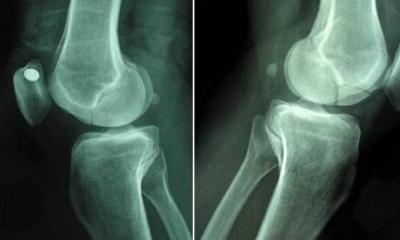

स्लीव्ह गॅस्ट्रिकॉमीमध्ये, वजन कमी करण्यासाठी सुमारे ७५ टक्के पोटाचा भाग काढून टाकला जातो. सायन्स डेलीच्या एका अहवालानुसार २००५ ते २०१९ या काळात स्लीव्ह गॅस्ट्रिकॉमीच्या माध्यमातून किशोरवयीन मुलांमध्ये वजन कमी होण्याच्या केसेसमध्ये १०० टक्के वाढ झाली आहे. आरोग्य तज्ञांचा असा दावा आहे की वजन कमी करण्याच्या या पद्धतीचा परिणाम हाडांवर (कमकुवत हाड) होतो.

सुमारे एक वर्ष किशोरवयीन मुलांच्या आरोग्यावर लक्ष ठेवल्यानंतर, संशोधकांना त्यांच्या वजनात १३ ते २८ किलो कमी दर्शविले. तसेच, त्याच्या हाडांमध्ये आणखी 'मॅरो फॅट' सापडले आणि कमरेच्या मणक्यात 'हाडांची घनता कमी होण्याची समस्या' दिसून आली.

डॉ. ब्रेडेला यांनी सांगितले की, ''स्लीव्ह गॅस्ट्रिकॉमीनंतर हाडांमध्ये हाडांची घनता कमी होण्याची शक्यता असते. हाडांची घनता गमावण्याव्यतिरिक्त हे आपल्या हार्मोन्स आणि शरीराला आवश्यक असलेल्या पोषक द्रव्यांवर देखील परिणाम करते.''